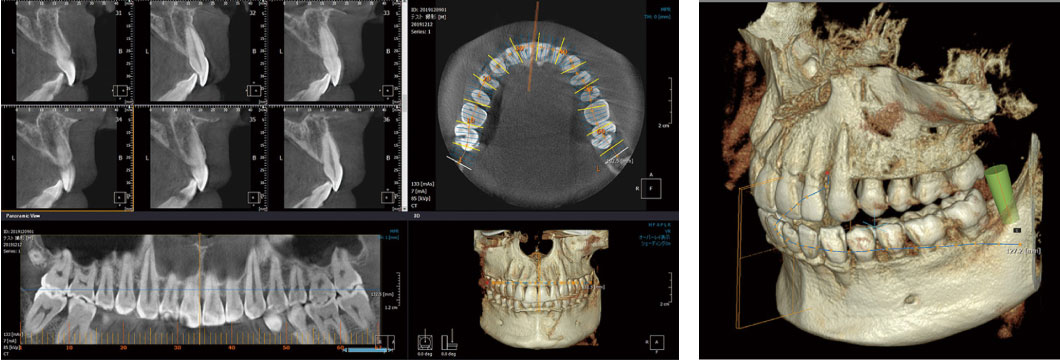

セファロ付き歯科用CT